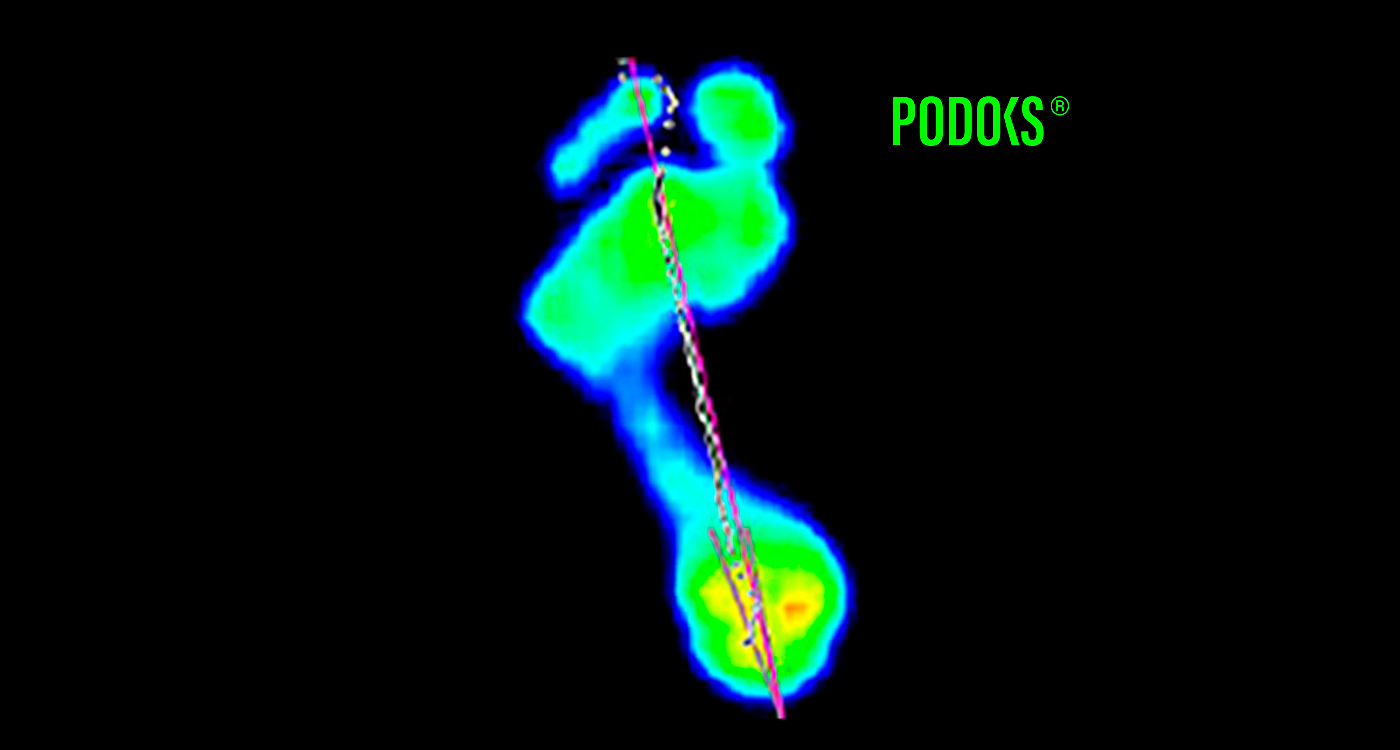

ANTES / DESPUÉS

Observa los beneficios de utilizar un calcetín con la tecnología de podoks.

(DESLIZA Y COMPRUÉBALO TÚ MISMO)

Con Podoks – En el mismo paciente, con el calcetín Podoks se observa la normalización del patrón de apoyo en el antepié, además de una separación del primer dedo respecto al segundo, mejorando su función biomecánica.

25%

REDUCE LA PRESIÓN PLANTAR

Además de reducir un 25% en las presiones plantares dinámicas bajo la cabeza del primer metatarsiano gracias a la tecnología de Podoks, también reduce un 23% la presión en el primer dedo gracias a la cuña de Hallux.